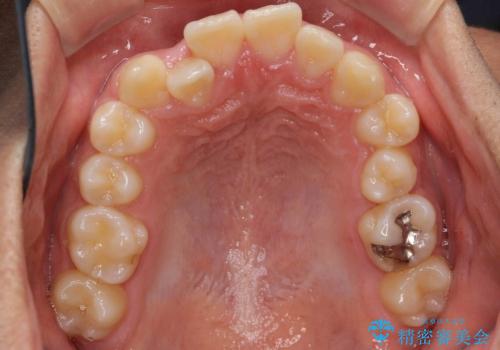

- ワイヤー矯正による治療後7年以上経過した患者様です。当時上の小臼歯を2本抜歯しています。

矯正後8年目になりますが、並びも綺麗に保持でき、また上下の歯がさらにしっかり咬んできているのがわかります。

下は歯につけるタイプのワイヤーを貼っています。

上は取り外し式の装置を就寝時使っていただいています。